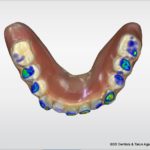

The final denture design was completed in the software. The lower teeth were intruded to not create excessive overbite.

From this design the laboratory is able to print try in dentures to test fit, bite, and tooth aesthetics. I chose not to have any pink added, but this is an option if you like.

I’d like to remind you this will be the patients second visit!

The printed try in dentures are quickly and easily relined with wash impression material for fabrication of the final prosthetic.